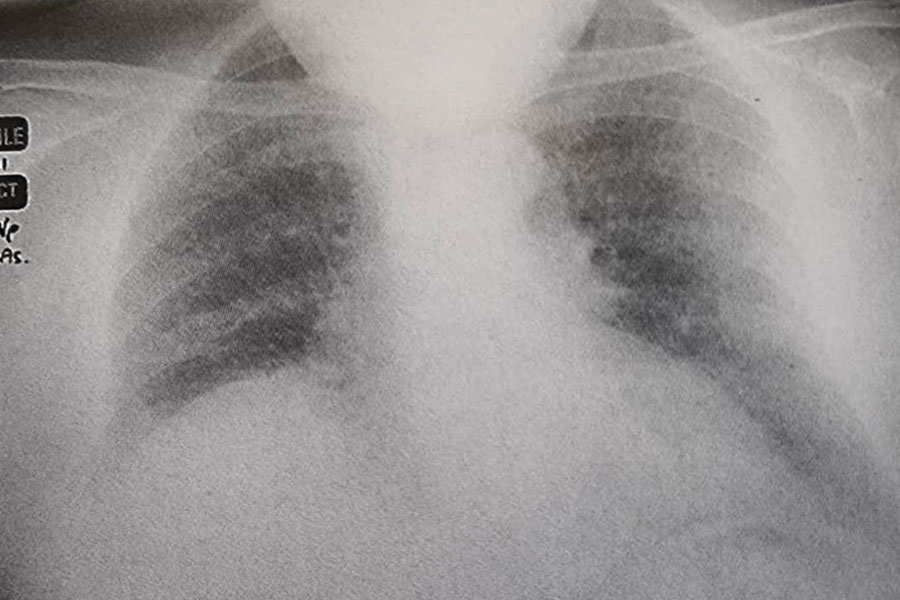

1. نظر شما در مورد رادیوگرافی قفسه سینه چیست؟ (شکل62a)

تغییرات دوطرفهای به صورت سایهاندازی رتیکولونودولار منتشر دیده میشود که با توجه به این شرح حال، با سل میلیاری (Miliary tuberculosis) مرتبط است.